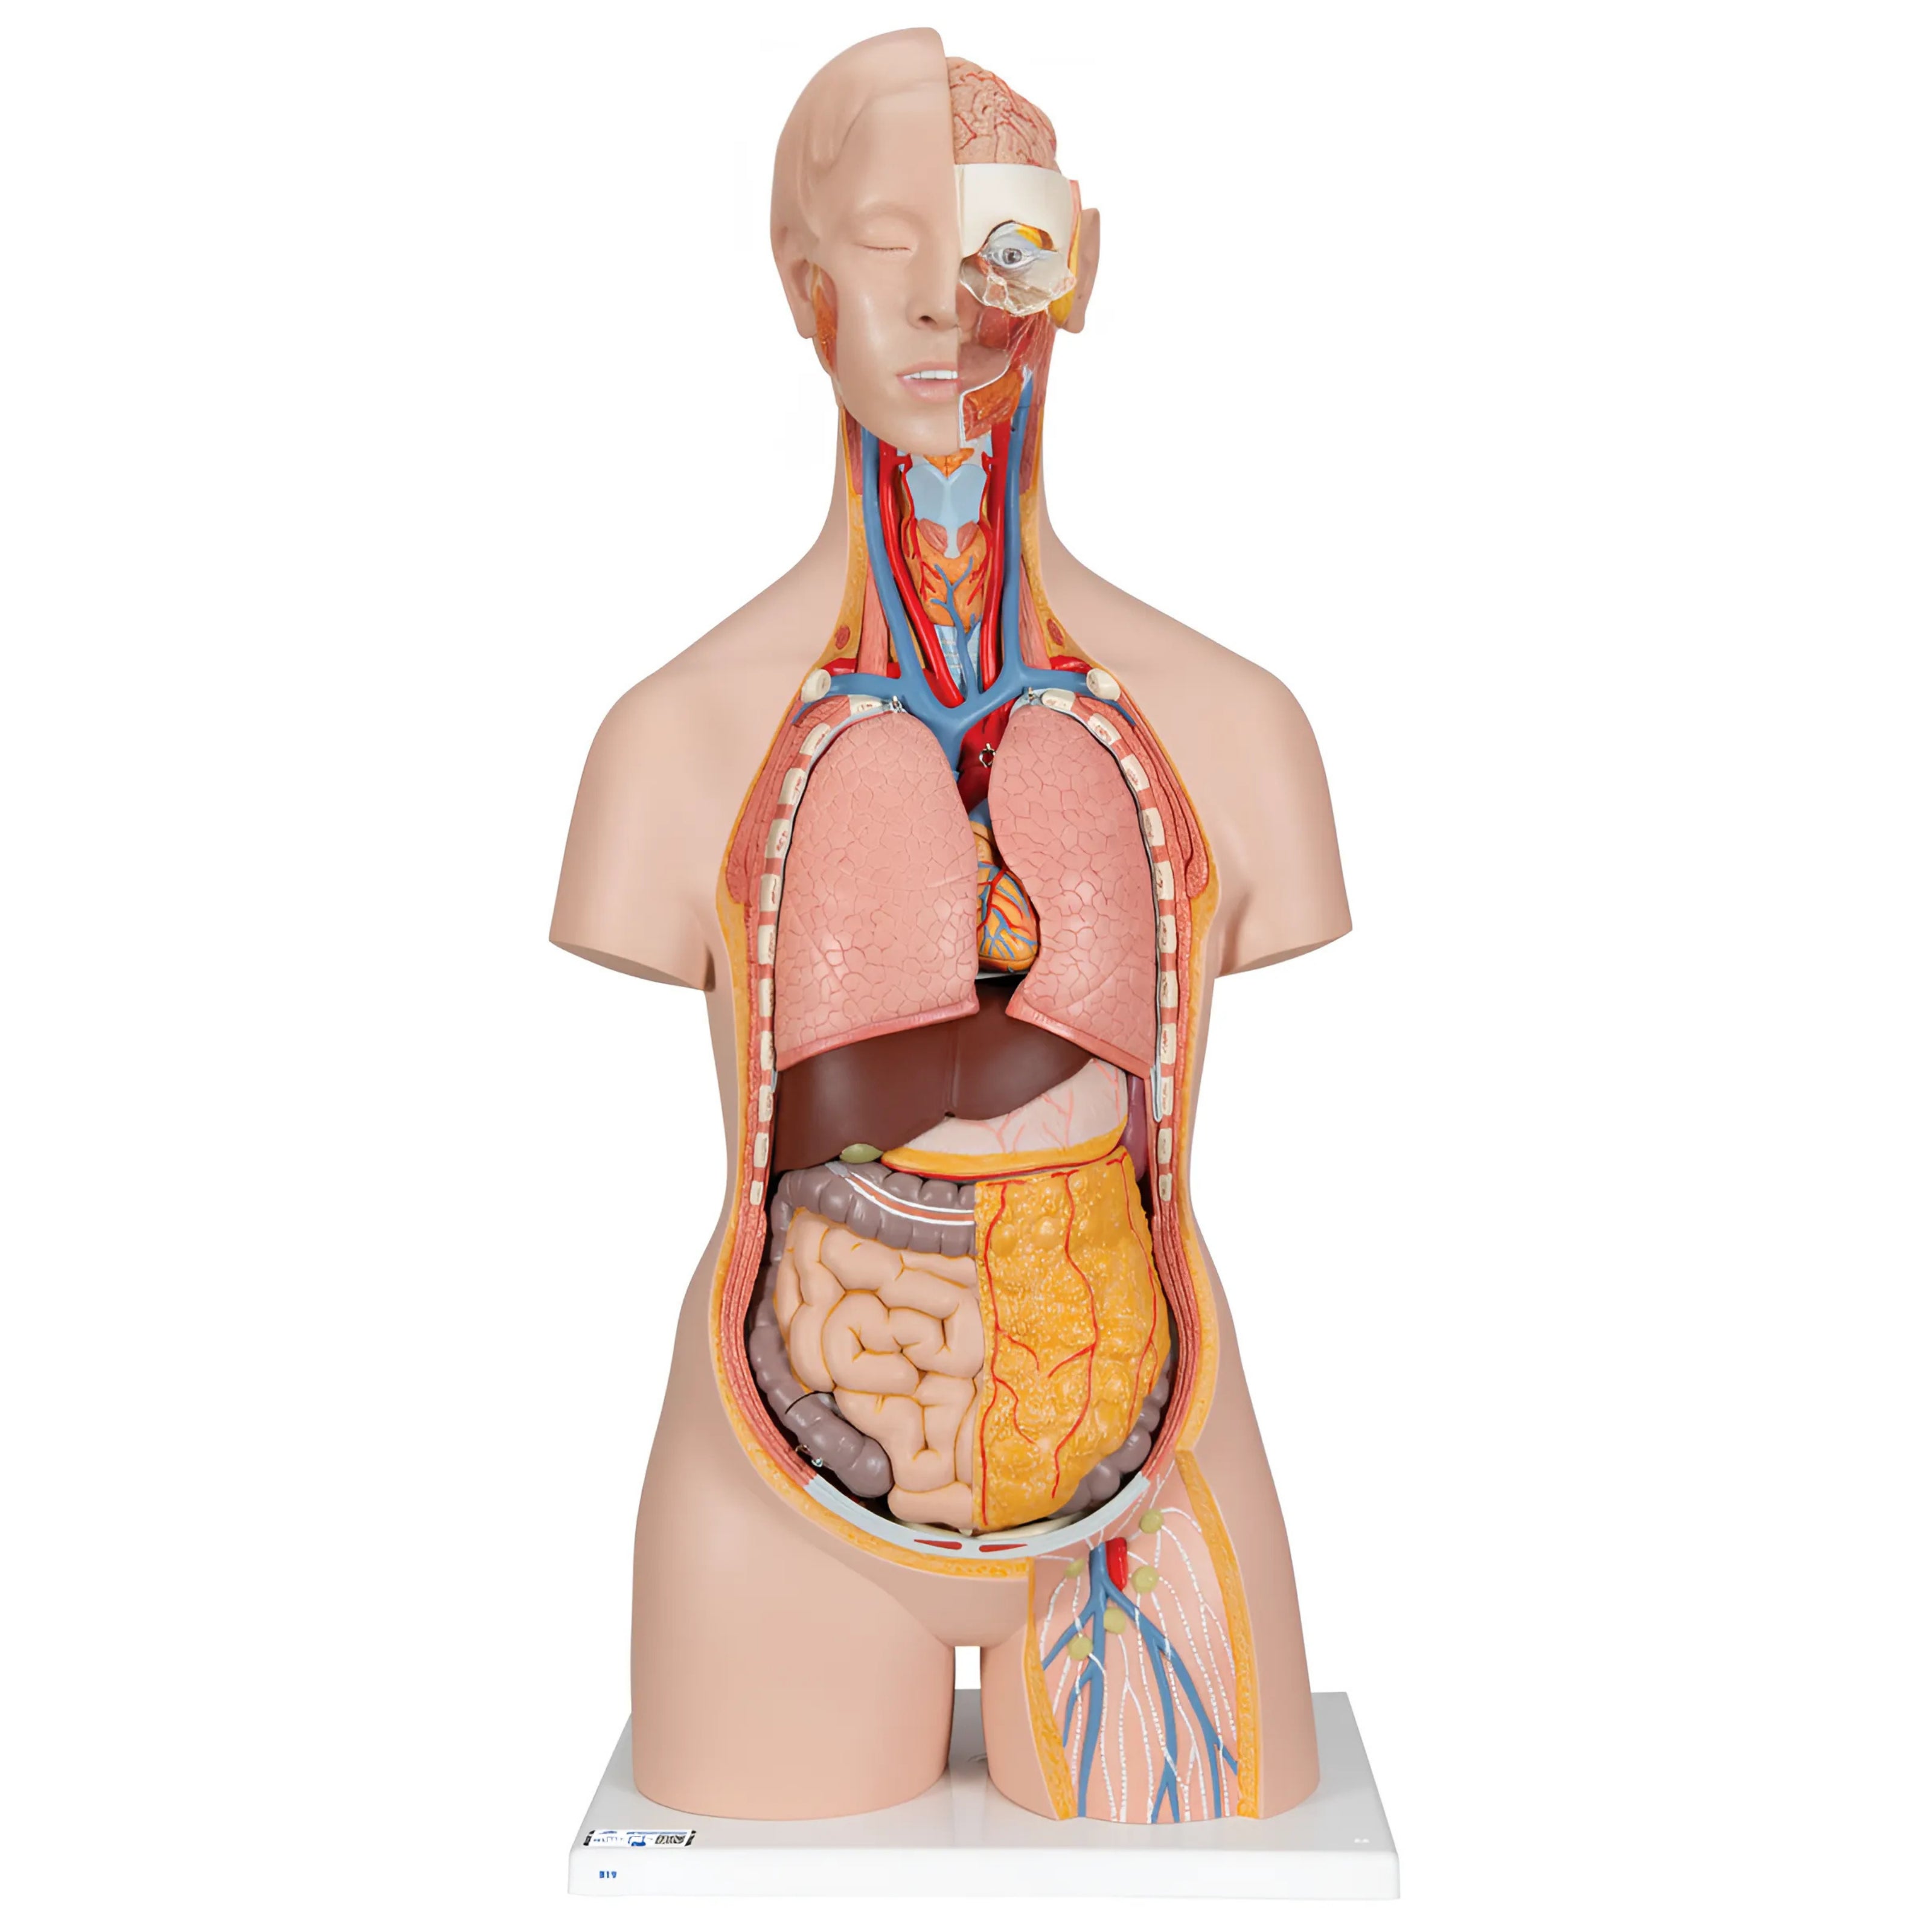

Torso clásico con espalda abierta, 18 partes - 3B Smart Anatomy

Precio de venta$33,762.96